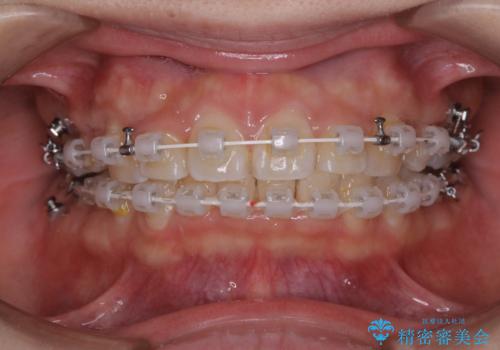

- 矯正装置

- 審美装置(ワイヤー)

- 治療計画

- 前歯のがたつきが気になるとご相談にいらした方です。当初は前歯の部分矯正をご希望されていましたが、全体的に整えることで審美的、機能的な歯並びとなりました。

当初は上顎前歯のみの部分矯正をご希望されていましたが、部分的に前歯のみを並べると出っ歯感がつよくなり、食事もしづらくなる可能性をお伝えしました。全顎的な矯正治療により、審美的、機能的な歯並びとなりました。